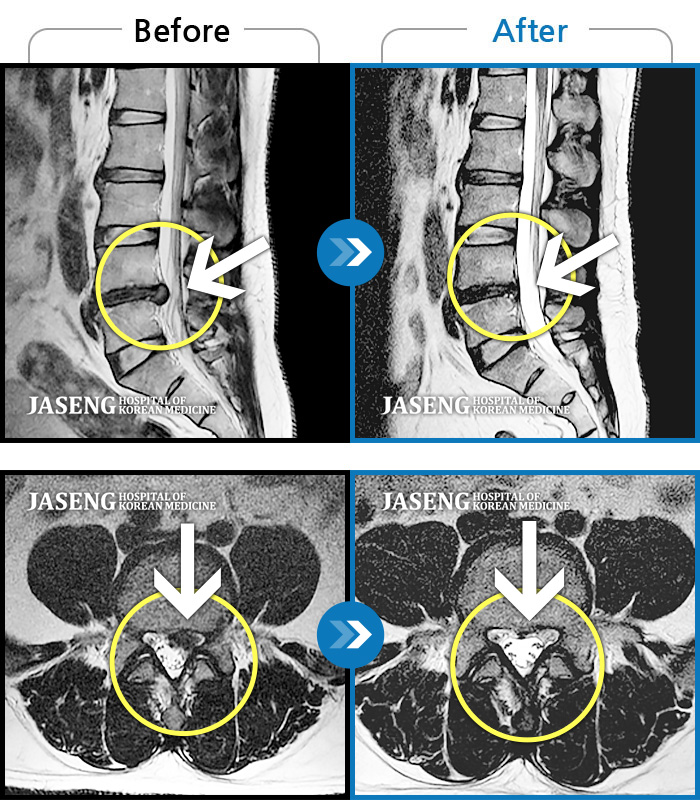

Before

After

환자에게 사전 동의를 받아 동일 조건에서 촬영되었습니다.

개인에 따라 치료 후 부작용이 발생할 수 있으니 의료진과 상담 후 치료를 진행하시기 바랍니다.

허리에서 골반으로 내려가는 심한 통증, 바로 눕기 어려운 상태

왼쪽 발목과 엄지발가락 힘이 빠지면서 허리 통증